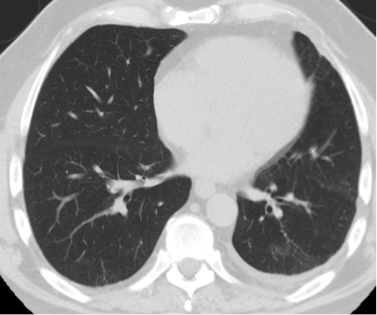

Case Presentation: A 63-year-old male presented to our institution with progressive dyspnea and associated hemoptysis of several days duration. He was a former cigarette smoker, having smoked approximately 1 pack per day for 45 years, who had recently transitioned to using electronic cigarettes, or “vaping,” 3 months prior. With regards to his vaping, he reported using both cannabidiol (CBD) and flavored solutions in attempts to abstain for further cigarette use. He had no recent respiratory illness and no documented history of malignancy, pulmonary embolism, COPD or other lung disorders. On admission, he was afebrile, oxygenating well and with stable hemodynamics. There was no leukocytosis and initial infectious work up was negative. Chest radiograph revealed a new left-sided pleural effusion. Subsequent CT angiogram of the chest and pulmonary arteries was without pulmonary embolism but confirmed the presence of the left-sided effusion. He underwent thoracentesis with the removal of 700 mL of serous fluid. Pleural studies were consistent with an exudative effusion by Light’s criteria. Cytology was negative for malignant cells. Repeat CT of the chest revealed an 8 mm pleural-based thickening on the right but no findings on the left. He was evaluated by pulmonology who recommended repeat CT imaging in 4 weeks and discontinuation of further electronic cigarette use. The patient felt significantly improved and repeat CT of the chest following abstinence from further vaping was without re-accumulation of the left-sided effusion. The pleural thickening noted on the right side appeared stable with no progression on repeat imaging.